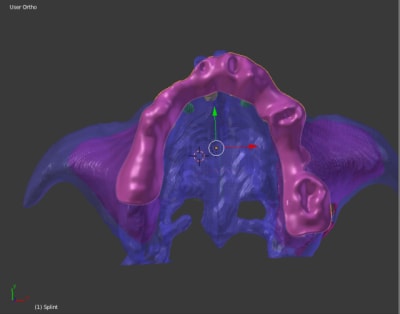

qu'est ce que vous pensez de ce guide, à mon avis il ne nécessite ni irrigation interne ni pins de rétention ( s'il est supra osseux) car rien qu'à l'aide d'un petit coup de marteau il s'enfoncera très bien sur l'Os avec une tres grande précision grace à sa structure trabéculaire.

Je vous invite à voir les autres images sur la Dropbox car elles sont très volumineuses et je n'ai pas pu les importer sur eugenol.

Je n'ai plus la collision dans le hardware .

Par contre j'ai un probleme pour lier le cylindre guide sur la base . Apparement tu as eu aussi ce probleme mais je n'ai pas compris la solution que tu as mise en oeuvre

lors du 1er essai tu as un message d'erreur

ensuite tu cliques sur la petite clé de la barre d'outil

et tu cliques sur la croix

cela fonctionne quand tu recommences !